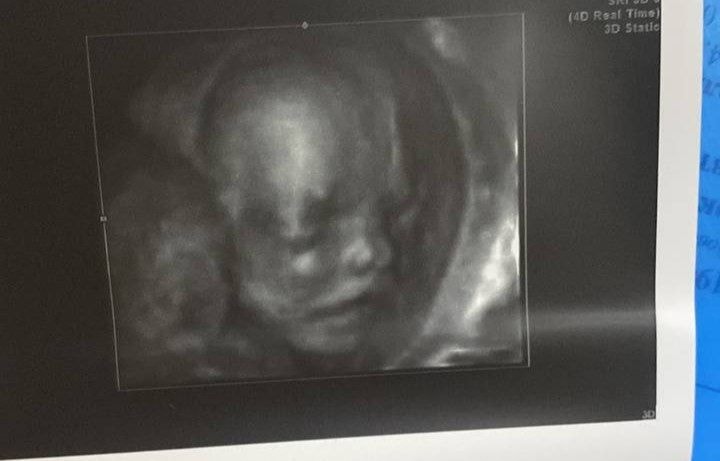

Веточка, вот вам разница 33 и 20 недель. Ничего не поздно. Изображение Изображение В 20 недель там уродец худенький 😁

11.10.2025